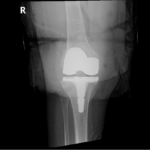

Your doctor will diagnose osteoarthritis based on the medical history, physical examination, and X-rays.

X-rays typically show a narrowing of the joint space in the arthritic knee.

The surgery is performed under spinal or general anesthesia. Your surgeon will make an incision in the skin over the affected knee to expose the knee joint. Then the damaged portions of the femur bone are cut at appropriate angles using specialized jigs. The femoral component is attached to the end of the femur with or without bone cement. The surgeon then cuts or shaves the damaged area of the tibia (shinbone) and the cartilage. This removes the deformed part of the bone and any bony growths, as well as creates a smooth surface on which the implants can be attached. Next, the tibial component is secured to the end of the bone with bone cement or screws. Your surgeon will place a plastic piece called an articular surface between the implants to provide a smooth gliding surface for movement. This plastic insert will support the body’s weight and allow the femur to move over the tibia, similar to the original meniscus cartilage. The femur and the tibia with the new components are then put together to form the new knee joint. To make sure the patella (knee cap) glides smoothly over the new artificial knee, its rear surface is also prepared to receive a plastic component. With all the new components in place, the knee joint is tested through its range of motion. The entire joint is then irrigated and cleaned with a sterile solution. The incision is carefully closed, drains are inserted and a sterile dressing is placed over the incision.